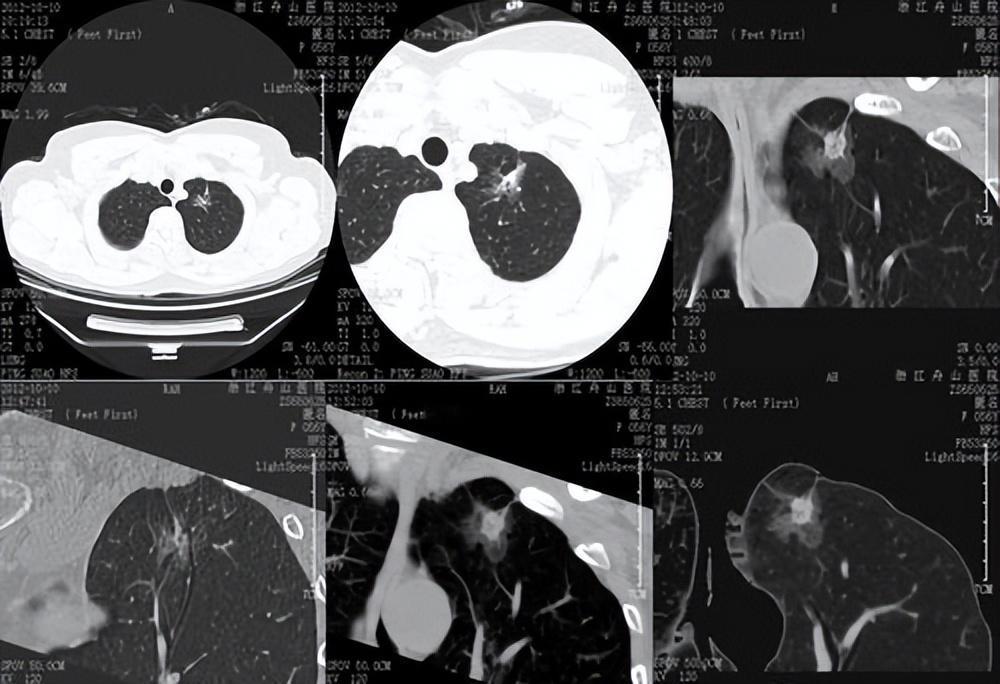

90% 的肺结节是良性,但那 10% 的 “危险分子” 恶变时会露出马脚!记住这几个特征,帮你快速识别: 1.形态变“怪异”:良性结节多是光滑的“小圆球”,恶变后会变成 “带刺的土豆”—— 边缘长出细小毛刺(像太阳日冕),表面凹凸不平(分叶征),有的还会拉着胸膜形成 “小尾巴”(胸膜牵拉),这 “三件套” 同时出现,恶性概率超 85%。 2.密度变“浑浊”:纯磨玻璃结节(淡云雾状)若出现实性成分,或混合磨玻璃结节的实性部分超过 50%,就像 “乌云变乌云夹冰雹”,恶变风险会大幅上升。 3.生长有“节奏”:良性结节要么长期不变,要么长得飞快(<30 天)。恶性结节多在 100-400 天内慢慢增大,比如半年内从 6mm 长到 8mm 以上,或增长速度越来越快。 另外要警惕“隐形信号”:痰中带血丝、莫名声音嘶哑超 2 周、手指末端膨大(杵状指),这些可能是结节恶变的 “远程警报”。 记住:结节大小不是唯一标准,形态和密度变化更关键!定期复查 CT,发现异常及时找呼吸科医生评估,早干预治愈率极高~